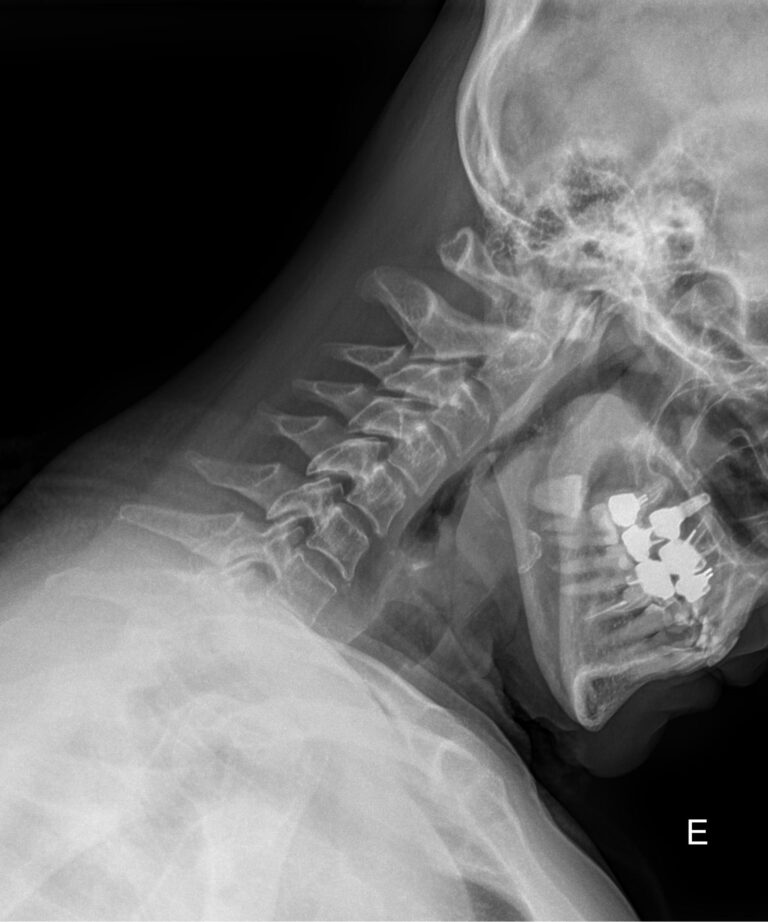

• Сохранение или сглаживание естественного лордоза в нейтральном положении, то есть на первом снимке;

• Смещение вперед или назад каждого позвонка по отношению к нижележащим при сгибании и разгибании;

• Деформацию передней стенки позвоночного канала из-за смещения позвонков;

• Сужения, расширения или отсутствие изменений межпозвоночных пространств;

• Изменения формы тел позвонков, наличие остеофитов;

• Аномалии развития.

В качестве подготовки необходимо снять все металлические украшения с шеи и головы, расстегнуть пуговицы и надеть защитную накидку. Диагностика выполняется в положении стоя или сидя, всего делается 3 снимка:

• В боковой проекции ― строго боком к детекторной пластине;

• В условиях максимального разгибания головы назад;

• В положении максимального наклона головы вперед.